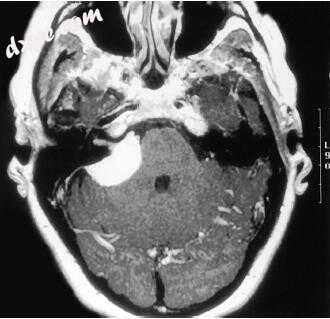

6.jpg

图-6. 钆增强磁共振图像显示2型神经纤维瘤病的双侧前庭神经鞘瘤特征。